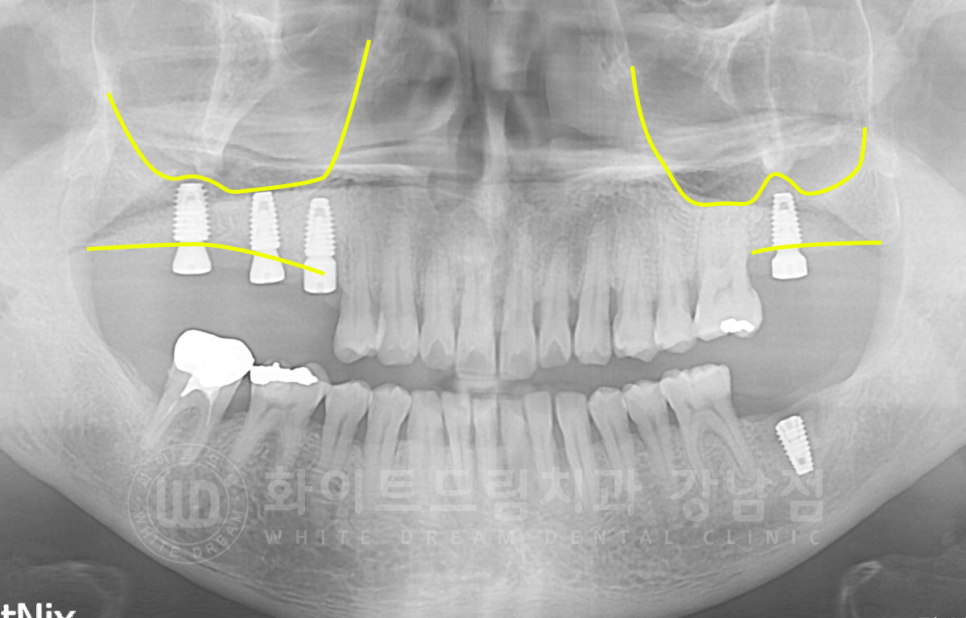

20번대 발치 후 x-ray입니다.

잇몸뼈가 심각하게 없는 편은 아니었지만, 임플란트가 식립되기에는 측면 & 수직 잇몸뼈가 조금 부족한 상태였기에

crestal 방식의 상악동 거상술을 동반한 뼈이식과 임플란트 식립을 진행했습니다.

골질이 나쁘신 편이 아니었고, 염증도 심하지 않은 상태였기에

10 / 20번대 임플란트는 1차 + 2차 수술을 한 번에 진행했습니다.

30번대 하악 어금니는 이식 뼈의 양이 많아 지연 수술로 1차 / 2차 수술을 따로 진행했습니다.

▲ 3개월 정도의 시간 차를 두고 임플란트 식립을 진행했습니다.

식립 후 잇몸뼈 측면이 두터워진 것이 확인됩니다.